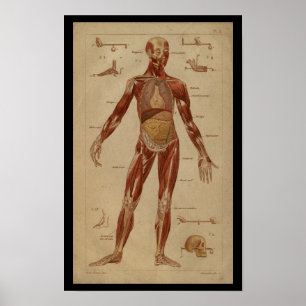

Impressão interno humano da anatomia do vintage

Preço18,25 €

Impressão 1902 interno humano do vintage da

Preço23,90 €